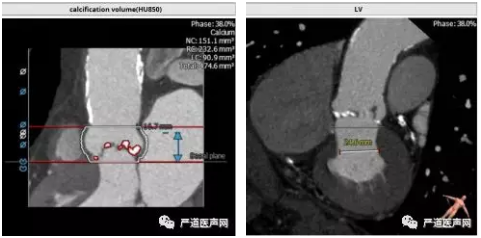

>>主动脉根部解剖:

三叶瓣,中度钙化,窦部结构尚可,冠状动脉高度尚可(LCA 16.7mm,RCA 14.8mm)。升主动脉弥漫性钙化,升主动脉高度40-50mm血管壁大量钙化并钙化中夹杂血栓,血管夹层风险较高。

根据患者术前 CT分析,这个病人瓣上 40-50mm 处主动脉弥漫性钙化,类似瓷化主动脉弓,钙化中夹有血栓,操作过程中主动脉夹层发生风险高。经术前讨论结合患者左室流出道解剖结构选择低位释放,规避升主动脉夹层风险,同时利用病人特有生理解剖结构规避术后瓣周漏的发生。同时根据四肢血管CT,选择右股动脉为主路径,选择 L29 规格VenusA-Valve 瓣膜。